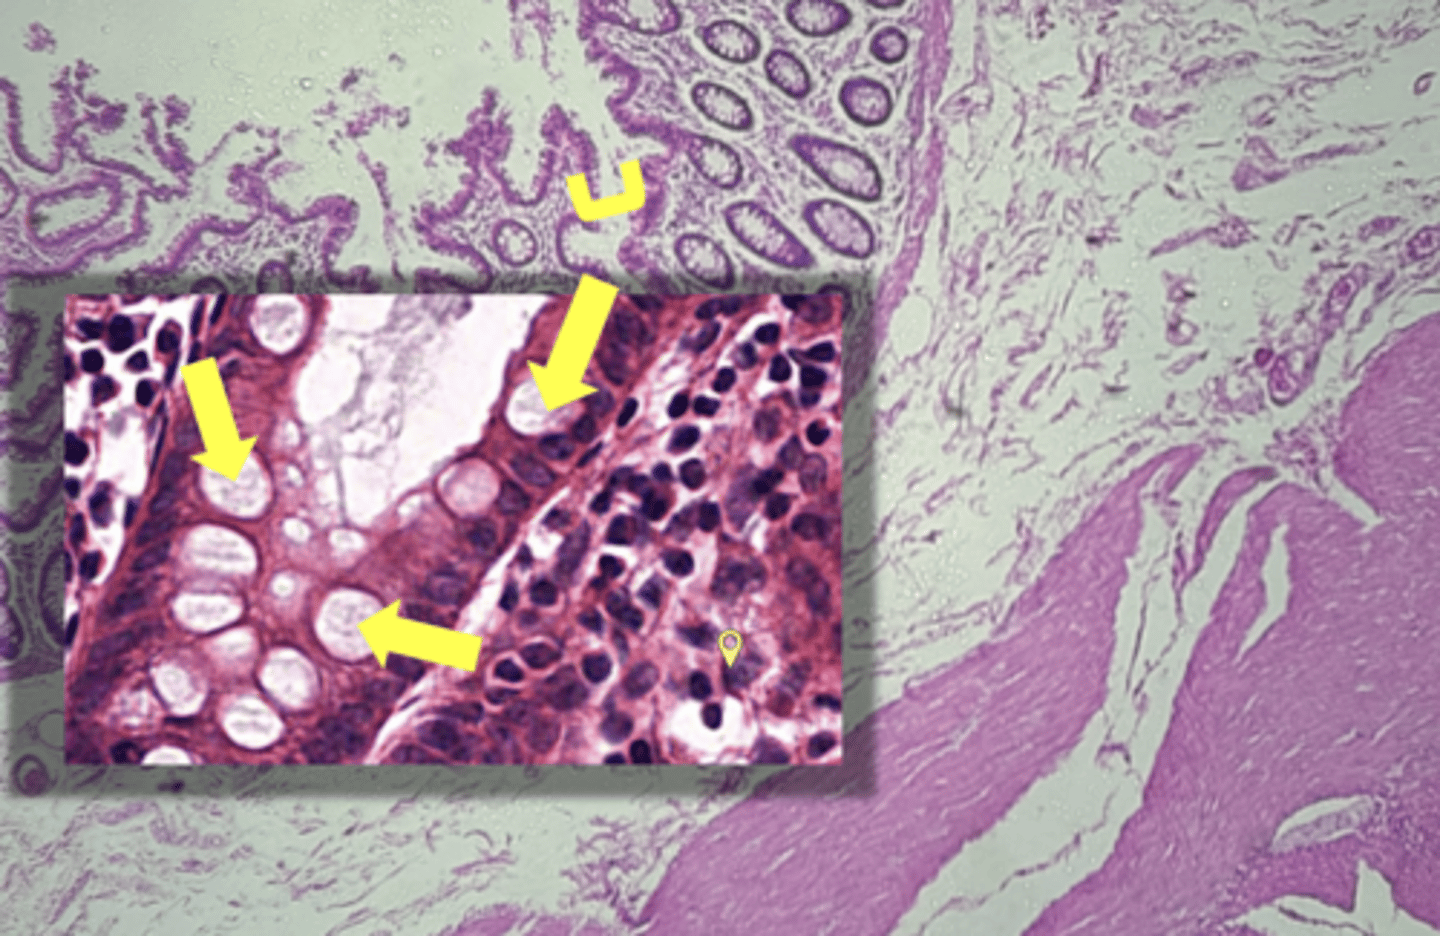

stomach

name the tissue

Parietal cells- HCl (hydrochloric acid)

(stomach)

name the cell & what it secretes

Chief Cells- pepsinogen/pepsin